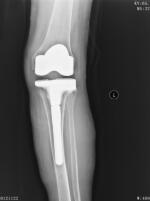

入院后完善各项检查,择期行左膝关节表面假体置换术,术中外侧平台骨质缺损较大,应用10mm垫片,加用胫骨延长柄(图3)。复查X线片(图4)示假体安装准确,左下肢力线良好,切口甲级愈合。术后1天指导患者行功能锻炼,逐渐下床负重行走,出院时左膝关节可屈曲110°。术后1年复查,左膝关节活动度0°~120°,稳定性良好,无疼痛不适,患者自我评价良好。

图3 左膝关节术中情况